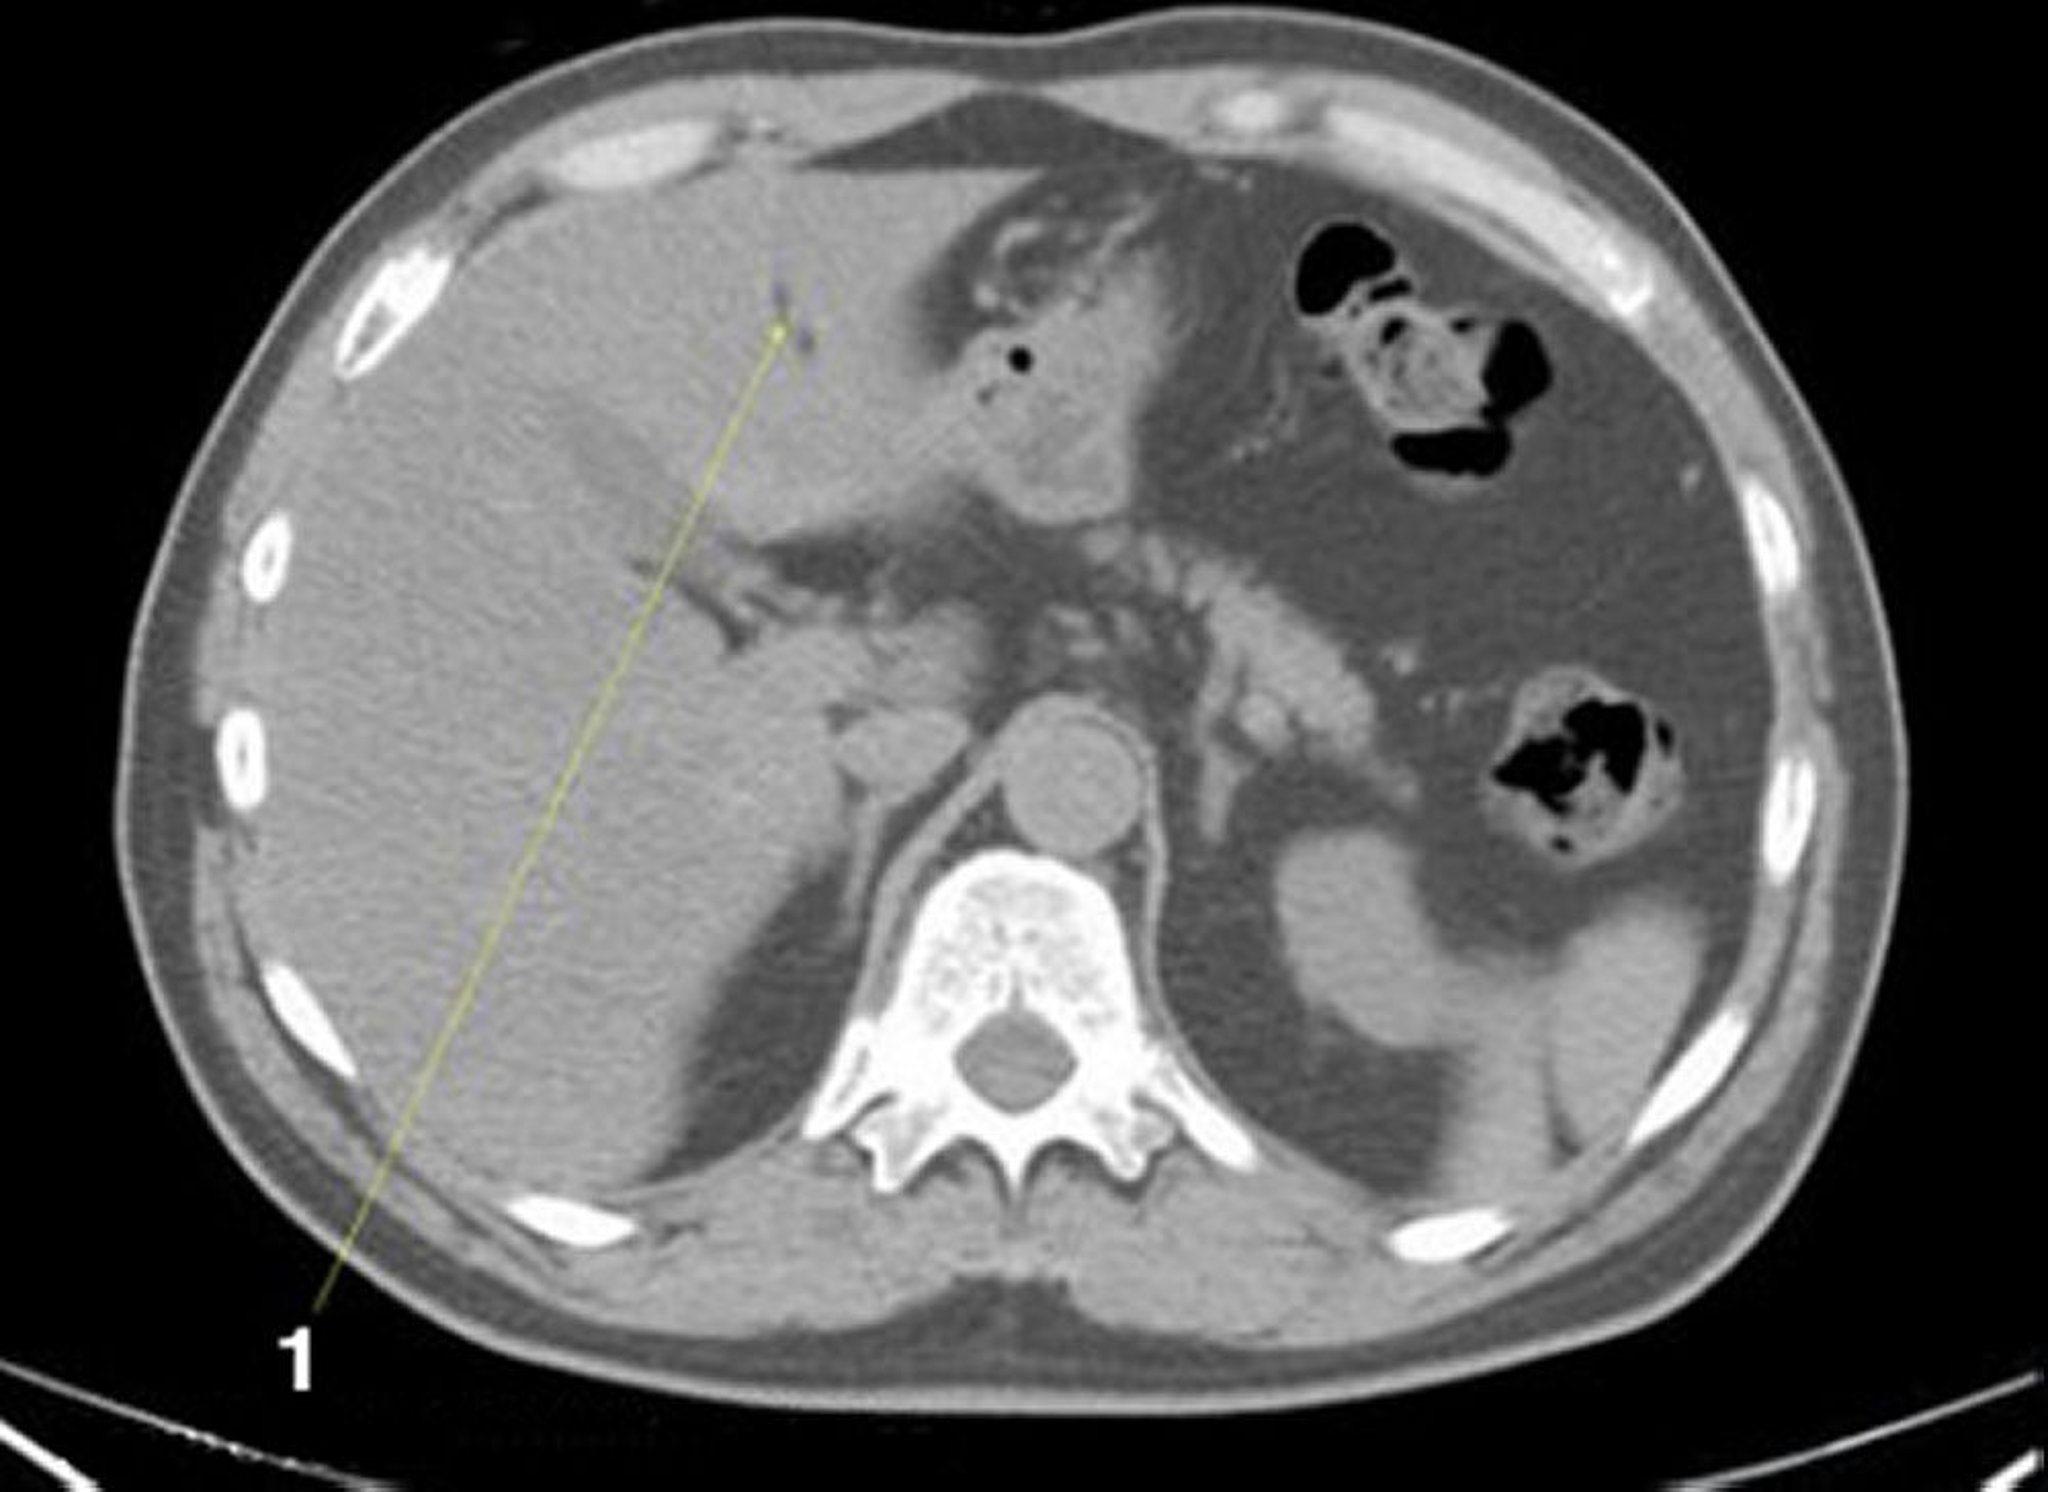

Noncontrast CT Scan of the Abdomen and Pelvis Showing Normal Anatomy (Slide 5)

1 = fissure for ligamentum teres.